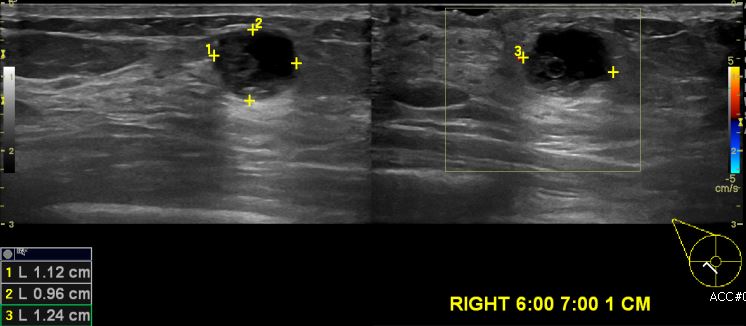

상기환자 우측 만져지는 멍울로 내원하신 50대 여성분으로 우측 유방 6시에서 7시 방향에 1cm 떨어진 거리에 만져지는 멍울 조직검사 시행하여 우측 침윤성 유관암 진단되었습니다.